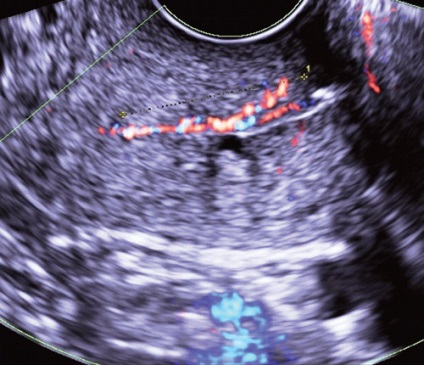

Érintkezése során ehometrosalpingografii alkalmazásával végzik, mint kontraszt steril sóoldatban is lehetővé válik láthatóvá a kis polipok az endometrium és az endometrium összenövések (ábra. 3). Az akusztikus alapja a lehetséges nem-invazív és ehogisteroskopii ehotservikoskopii teremt serometra, például posztmenopauzális elzáródás külső os (ábra. 4), vagy, amint azt a fentiekben megjegyeztük, a fokozott nyálka termelődés a cervikális végén a proliferatív fázis a menstruációs ciklus. Mivel a váladék az időszakban bizonyos esetekben állnak vizualizációs és polipok, lokalizált a külső os. Hematometra és / vagy gematotserviks, mert a szervezet folyamatai vérrögök kevésbé informatív, mint ennek fényében fibrin vérrögök és polipok nehéz lehet megkülönböztetni a normál B-mód (ábra. 5, 6).

A különböző szállítási módok és a Doppler véráramlás képalkotó nedopplerovskoy valóban lehetővé teszi számunkra, hogy azonosítsuk a vaszkuláris kocsány a polip (ábra. 9), kivéve, ha nincs jele a hámlás az endometrium. Ebben az esetben a (ábra. 10) mozgását a vér az üregben a méh és a méhnyak lehet szimulálni a vér áramlását az erek a polip lábak és regisztrált a készülék kijelzőjén, mint egy hasonló színjelek.

Ábra. 10. A mozgás a vér az üregben a méh a háttérben a endometriális hiperplázia regisztrálva a CDM üzemmódban.